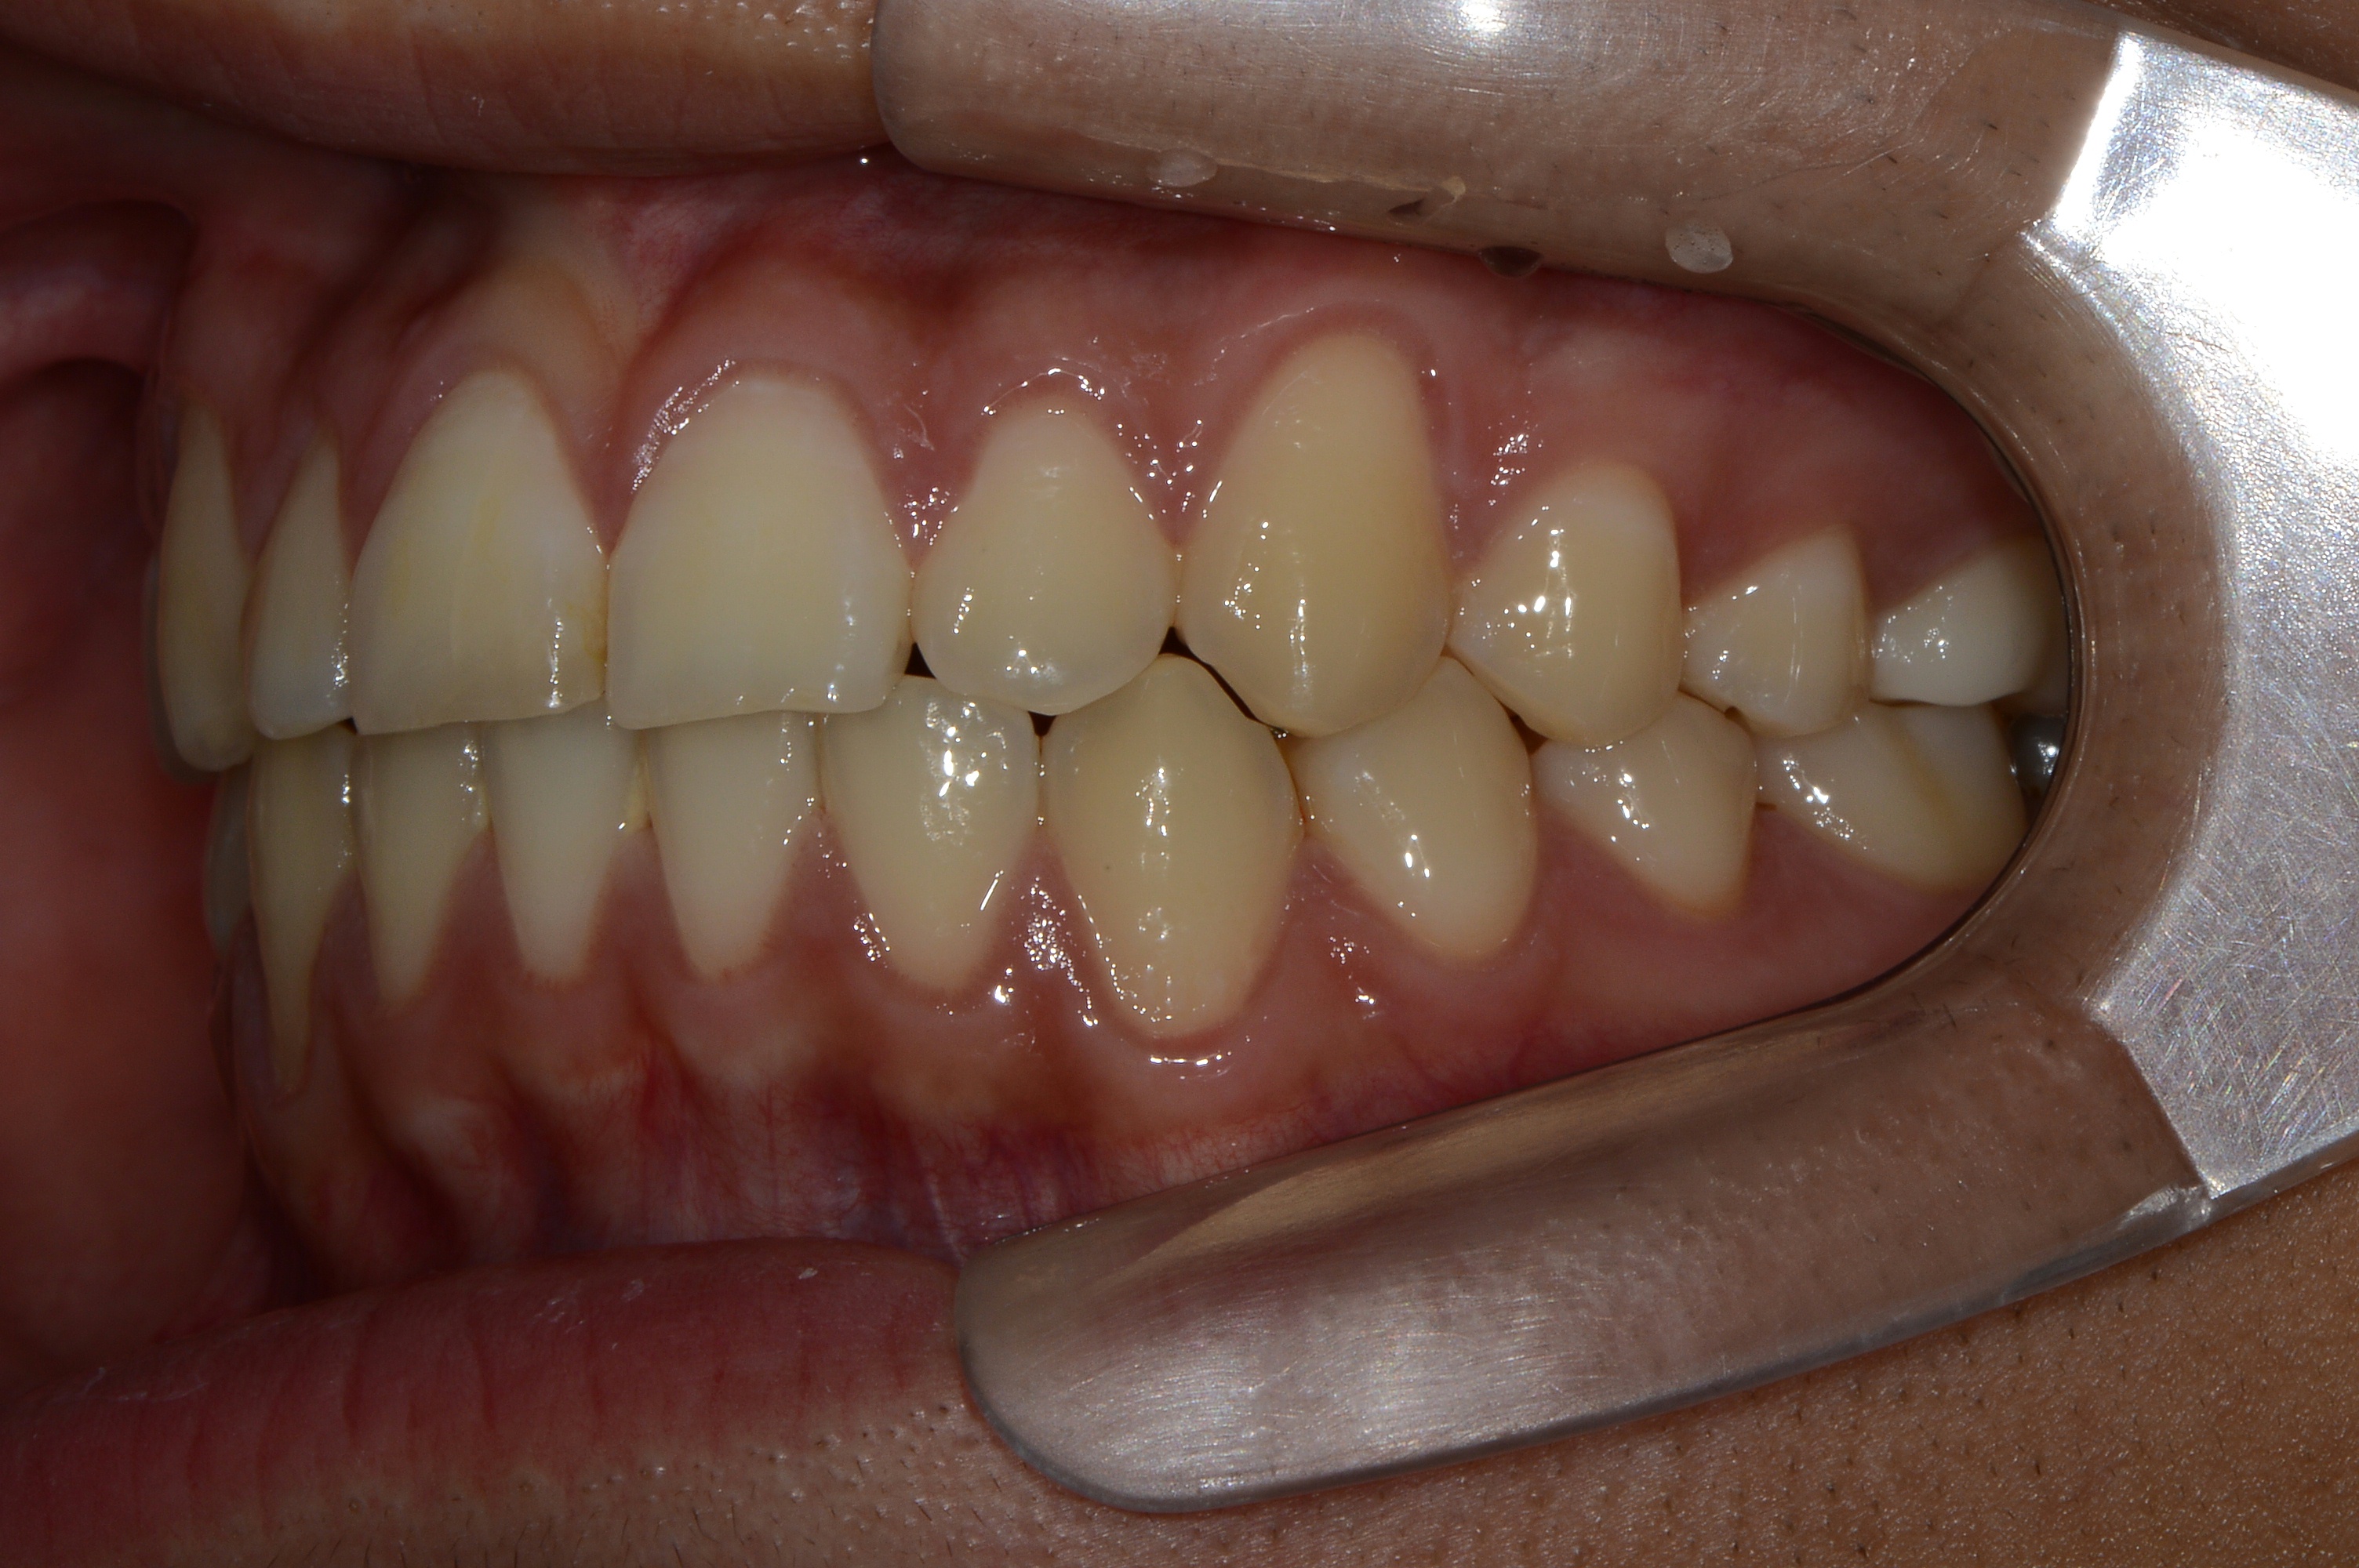

치료 전 사진입니다.